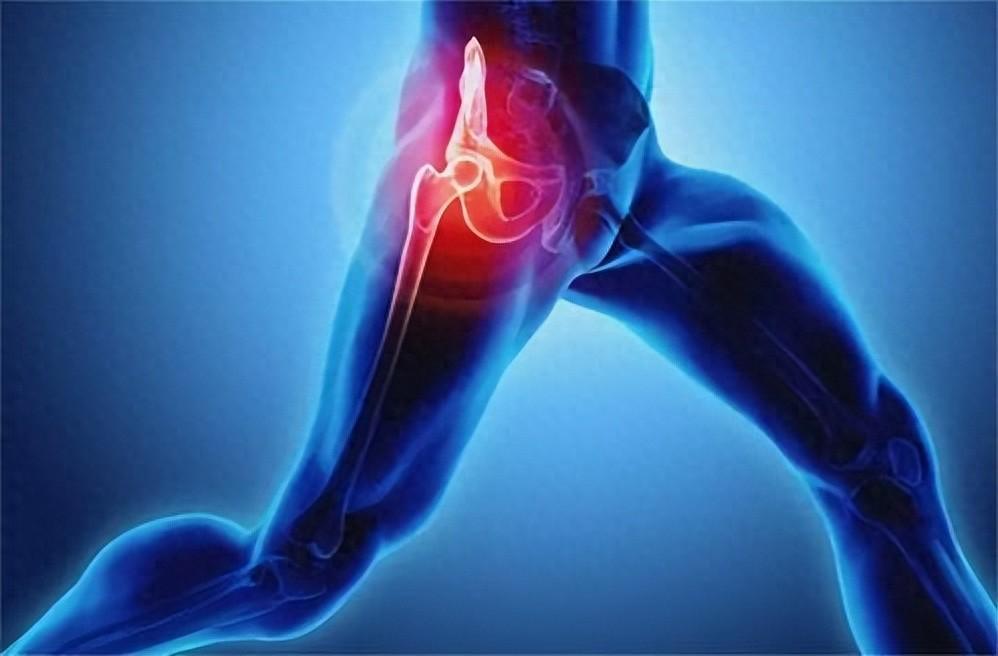

▼4. 匙狀指甲

若指甲看起來是匙狀,則可能代表患上了小細胞低色素貧血症,即紅血球比正常還要淡色。此外,也有可能是患上了血色沉著病,一種因為鐵過剩的肝臟病症。同時,匙狀的指甲也可以說心臟病或甲狀腺功能減退而出現的症狀。